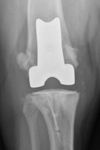

Treatment of cranial cruciate ligament deficiency is the most common surgical procedure performed in veterinary orthopedics.

Cranial cruciate ligament (CrCL) rupture is the most common cause of hindlimb lameness in dogs.